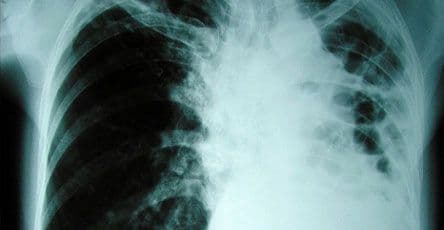

Dijagnostika TBC-a se vrši na osnovu RTG snimka, mikrobiološke dijagnostike uzorka sekreta, bronhoskopije i patohistologije. Nakon utvrđene dijagnoze započinje se liječenje,u bolničkim uslovima (izolovani od zdravog stanovnistva).